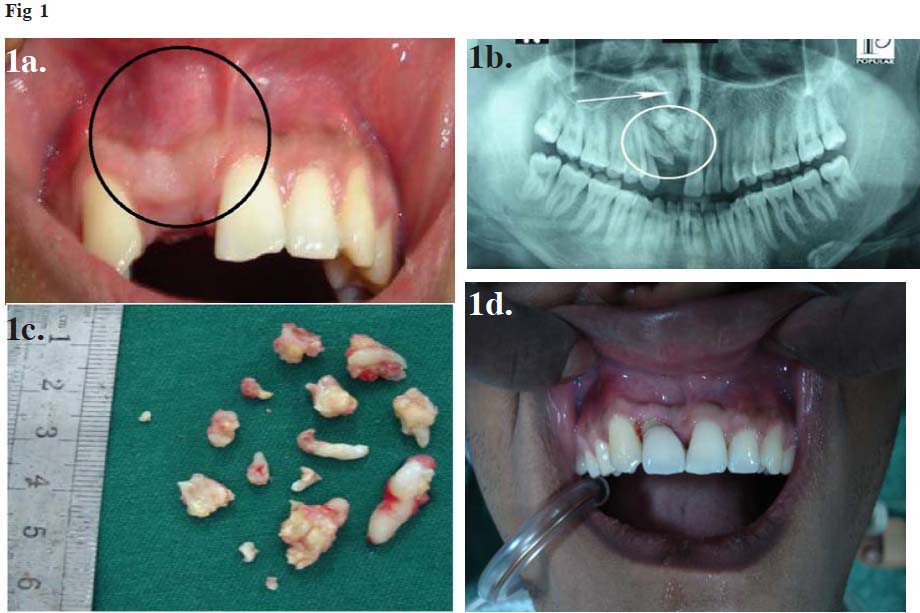

A 21-year-old- man reported to the Department of Dentistry, BIRDEM Hospital, Bangladesh, with the complaint of missing upper right central and lateral incisors and hard swelling on apical region of that missing alveolus. He had normal shedding of upper deciduos central and lateral incisors teeth at the age of 6-8 years and since then no permanent dentition of upper right central and lateral incisors occured. The patient was healthy and well developed with an unremarkable medical history. He had no history of trauma to oro-facial region or dental extraction. There was no family history of unerupted teeth or hypodontia. Extra oral examination revealed no abnormality in the upper lips as well as in the right side of the maxilla. Intra oral examination revealed a well defined gingival hard swelling which was palpated in the apical area of unerupted incisors (Figure -1a). No inflammatory change was noticed on the overlying and marginal gingiva and interdental papilla. The space for the eruption of the maxillary right central incisors was naturally maintained in the dental arch but the space for lateral incisor was reduced due to medial drifting of maxillary right canine. No midline deviation was diagnosed in comparison to the dental arch and the facial midline. There was no regional lymphadenopathy. An intra oral periapical and panoromic radiograph revealed impacted lateral incisor with multiple radio-opaque structures around the crown of the unerupted incisors region obstructing the eruption of the tooth (Figure -1b). The mass was surrounded by a narrow radiolucent zone. On the basis of clinical examination and radiological evaluation, the case was diagnosed as a compound odontome with impacted lateral incisor. Surgical removal of the odontome, extraction of impacted lateral incisor and its re-implantation was planned.

Prophylactic antibiotics were started 2 days before the surgery. Under local anesthesia, a labial mucoperiosteal flap was raised up to the extension of nasal aperture in upper incisor region. The layer of bone overlying the labial surface was removed and the calcified mass was exposed and 15 pieces of calcified tooth like structures were removed without disturbing the underlying tooth (Figure -1c). Curettage with debridement was done without leaving any remnants. Then the impacted lateral incisor was extracted and preserved in normal saline. Retrograde filling was done with zinc free alloy taking care not to damage periodontal ligaments. Root canal treatment followed by re-implantation of preserved extracted lateral incisor was done. To avoid damage to the deeper structure, central incisor was not removed. Immobilization of re-implanted lateral incisor was done with adjacent teeth by 0.7 SS wire. The wire for immobilization, filling and suture materials were removed after 21 days.

Fig 1: (a): Missing upper right central and lateral incisors and a hard swelling on upper right anterior part of alveolus. (b): X-ray OPG shows  a calcified mass with multiple teeth like structures with impacted right lateral incisor, arrow indicates central incisor. (c): 15 pieces of tiny tooth like structure. (d): Final esthetic appearence   after surgical removal of odontome and re-implantation.

After 3 months, the re-implanted lateral incisor was assessed clinically and radiologically. There was no significant mobility. Periapical radiograph showed new bone formation around the root of the re-implanted tooth. For esthetic purpose, a porcelain crown having a shape of central incisor was made on the lateral incisor (Figure-1d). A Maryland bridge was selected to distribute the occlusal load applied on the lateral incisor.